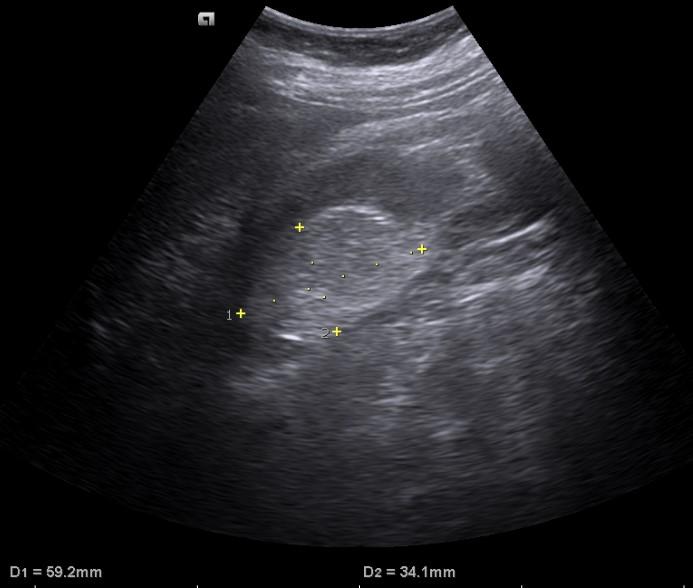

Case of the Week 32 2016 *58-year-old female. What is the most likely diagnosis? Answer: Renal angiomyolipoma Kategori:Cases Önceki yazı Case of the Week 30 2016 Sonraki yazı Case of the Week 5